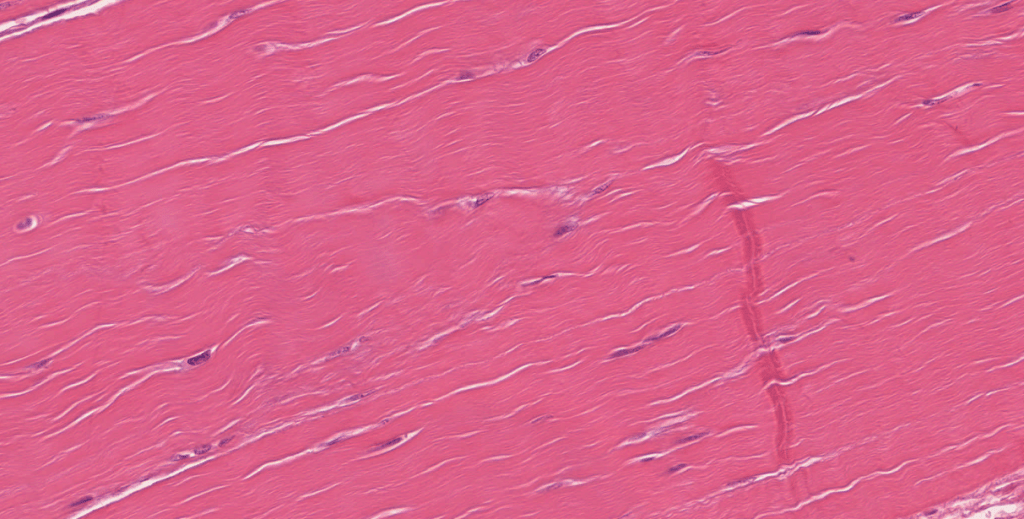

CÉLULAS RESIDENTES Y TRANSITORIAS

Residentes: mastocitos, fibroblastos, adipocitos, macrófagos.

Transitorias: plasmocitos y leucocitos (neutrófilos, linfocitos, monocitos, eosinófilos, basófilos)